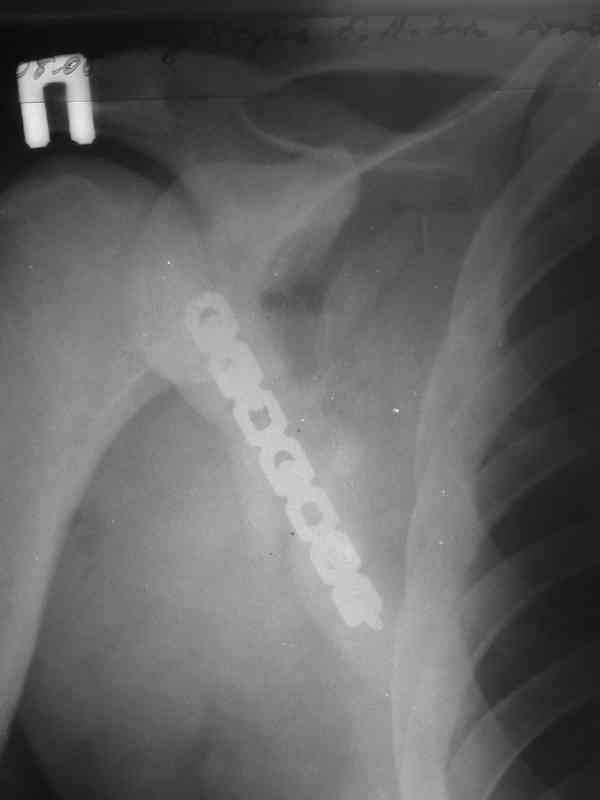

К сожелению доктор который занимается грудной клеткой в отпуске, у себя нашёл только вот этот снимок

С Уважением А.Миронов

Всё зависит от типа нестабильности грудной клетки. Стабилизация проводится от 4 по 8 активно участвующих в дыхании рёбер. Т.е если имеется "створка" фиксируютс рёбра по одноё линии. Разрез продольный по линии переломов из которого фиксируются 2-3 ребра, если имеется "клапан", то фиксируютяс 2-3ребра по одной линии и 2-3ребра по другой линии. Репозиция несложная, фиксация реконструктивной пластиной, в хрящевой части лучше LCP.